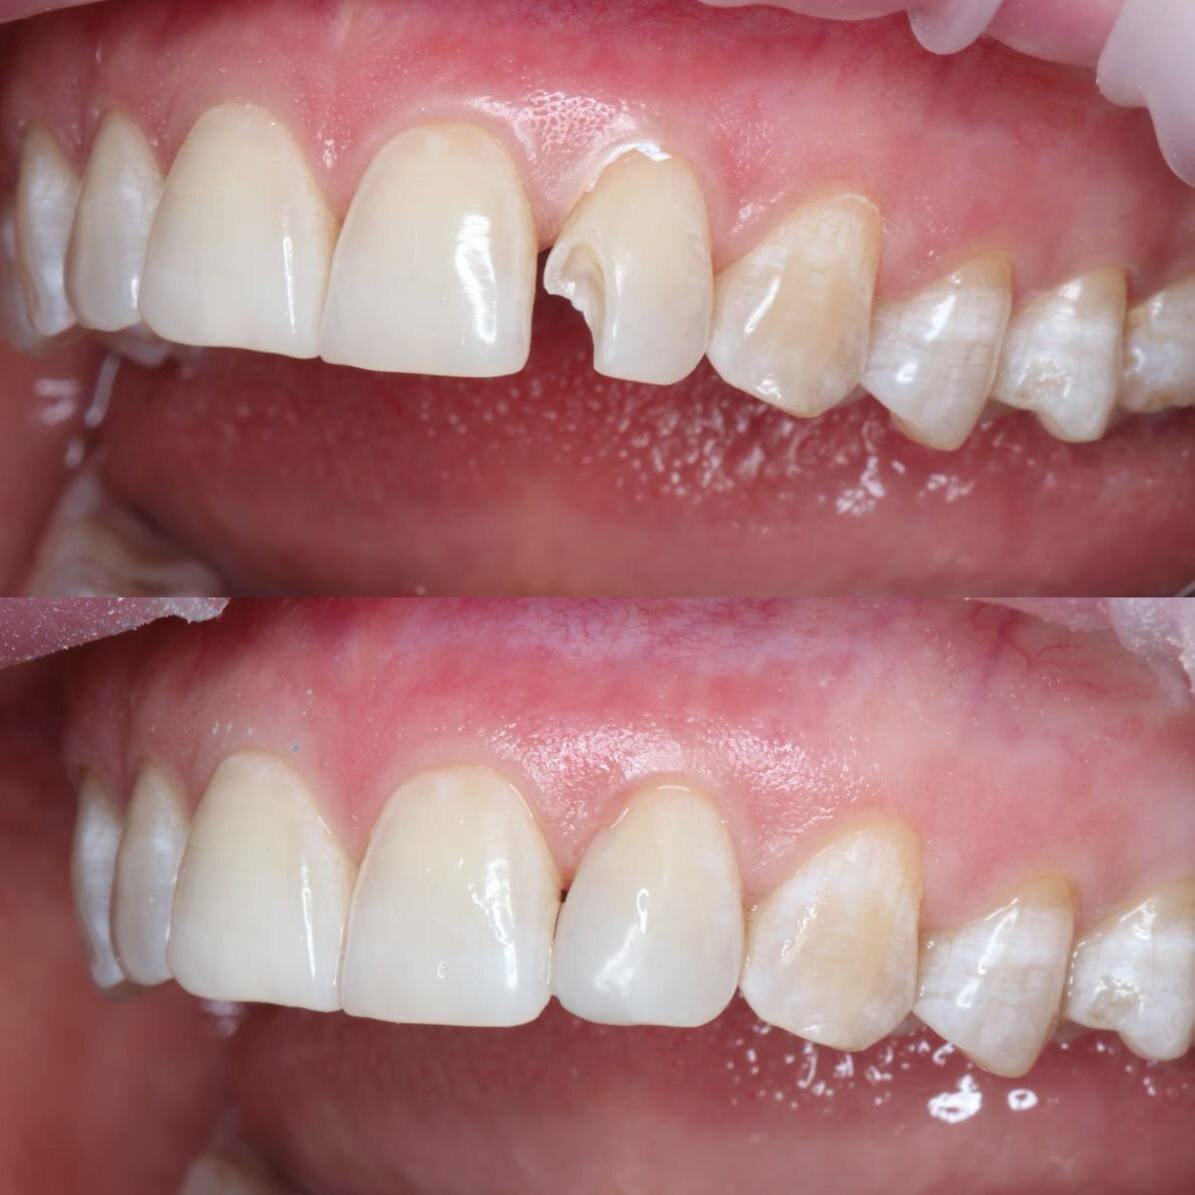

Gold Dent специализируется на различных направлениях стоматологии: общей терапии, хирургии, ортодонтии, эстетической и детской стоматологии, имплантологии, протезировании и эндодонтии. В клинике применяются передовые технологии, такие как цифровая стоматология CAD/CAM, лечение под микроскопом, компьютерная томография и костная пластика.

- Долговечные и эстетичные результаты (импланты, протезы).

- Быстрое и безболезненное пломбирование.